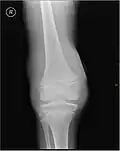

Lipohémarthrose (présence de sang et de graisse dans l'épanchement hémorragique) est une fracture articulaire du plateau tibial interne. La flèche indique un niveau de liquide entre le composant gras supérieur et le composant sanguin inférieur.

L'hémarthrose est un épanchement de sang dans une cavité articulaire consécutif d'une lésion ligamentaire, d'une fracture osseuse ou encore d'une atteinte du cartilage osseux[1]. Cette physiopathologie est caractéristique des personnes atteintes d'hémophilie sévère et dans une moindre mesure chez les formes modérées, car chez les hémophiles, l’absence ou l’altération d’un des facteurs de la coagulation (VIII ou IX selon le type d’hémophilie) perturbe le processus de la coagulation, au point qu’un traumatisme minime peut provoquer un saignement prolongé[2]